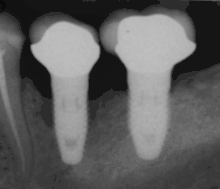

أشعة توضع استقرار الغرسات بالدعامات